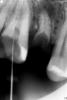

Dandan Опубликовано 7 июня, 2011 Поделиться Опубликовано 7 июня, 2011 (изменено) Здравствуйте, уважаемые коллеги! Нужен ваш совет. Ситуация следующая: зуб № 16. 2 канала, нет намека на 3-й. с небным никаких проблем, щечный непроходимый, плюс ко всему фуркация подвижна. камеру вскрывала я, не было риска перфорации, сразу вскрылись 2 канала. рентген аппарат у меня не очень, так что снимки некачественные. я первый год как работаю, не сталкивалась с такой ситуацией. не могу разобраться в зубе, и не знаю что с ним делать.оставила метапасту в зоне фуркации, у пациента жалоб нет. посоветуйте, как быть... sumare2.bmp Изменено 7 июня, 2011 пользователем Dandan Ссылка на комментарий

Kivilgar Опубликовано 7 июня, 2011 Поделиться Опубликовано 7 июня, 2011 Здравствуйте, уважаемые коллеги! Нужен ваш совет. Ситуация следующая: зуб № 16. 2 канала, нет намека на 3-й. с небным никаких проблем, щечный непроходимый, плюс ко всему фуркация подвижна.Подвижная фуркация- это да... Скорее всего там дентикль и под ним каналы найдете. Ссылка на комментарий

zybnaya feya Опубликовано 7 июня, 2011 Поделиться Опубликовано 7 июня, 2011 Подвижная фуркация- это да... Скорее всего там дентикль и под ним каналы найдете.+100 Дентикль скорее всего мешает обзору. уз уберите его и найдете вход даже в МБ2)) http://s15.radikal.ru/i189/1106/0f/e4165d55d7f1.jpg Ссылка на комментарий